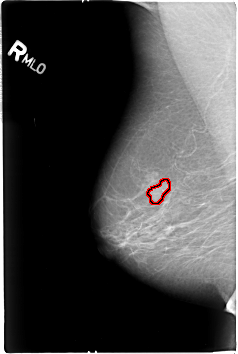

B_3015_1.RIGHT_MLO

FILE: B_3015_1.RIGHT_MLO.OVERLAY

TOTAL_ABNORMALITIES 1

ABNORMALITY 1

LESION_TYPE MASS SHAPE LOBULATED MARGINS OBSCURED-ILL_DEFINED

ASSESSMENT 3

SUBTLETY 3

PATHOLOGY MALIGNANT

TOTAL_OUTLINES 1

BOUNDARY